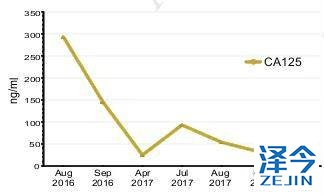

因此,患者开始接受每日80mg的奥西替尼AZD9291治疗,患者在一个月内达到了病情稳定(SD),CA125水平迅速下降,经过8个月的无进展生存期,患者肺左下叶出现新的病灶,胸腔积液增多,病情发展。

布加替尼联合西妥昔单抗治疗,病情长期稳定控制

患者再次基因检测发现T790M-C797S顺式突变,因此在2017年7月开始联合使用布加替尼(90mg/日)和西妥昔单抗(600mg/月),治疗一个月时,患者的疲劳和呼吸困难明显改善,CA125水平明显下降,直到2018年4月病情一直稳定(PFS为9个月),除了轻度疲劳外无其他的不良反应。虽然在2018年4月患者出现脑转移灶,但在2018年9月,患者的胸部病灶依旧得到很好的控制。